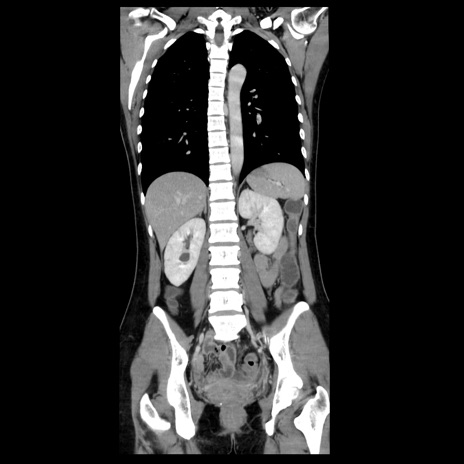

症例39(冠状断像)

【症例】40歳代女性

【主訴】上下腹部痛

【現病歴】2日目から下腹部痛あり。夜間は痛みで眠れなかった。昨日より上腹部痛と下痢が出現。臥位で痛みは軽快したため、休んでいた。本日になって臥位でも立位でも痛みが強くなってきたため救急要請。

【既往歴】子宮内膜症

【身体所見】部:平坦・軟、左上下腹部に圧痛あり、反跳痛あり。

【データ】WBC 21800、CRP 26.78

CT